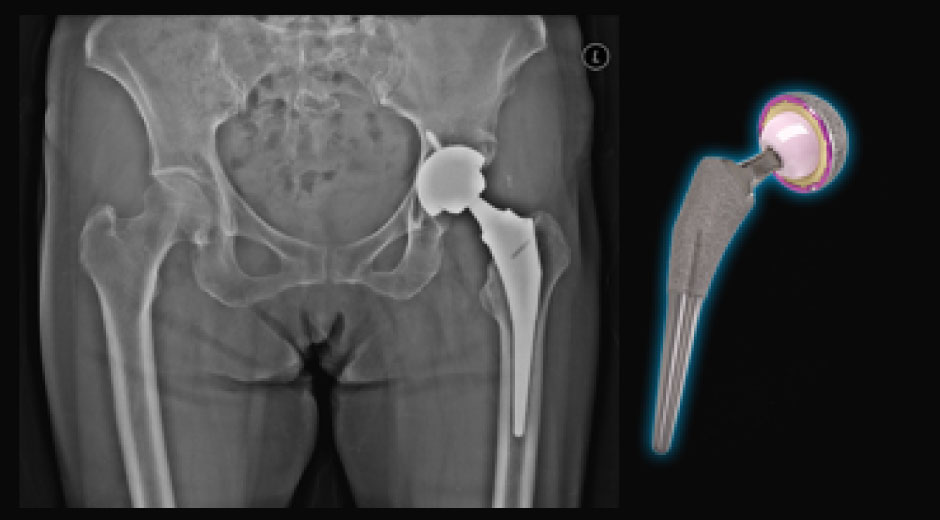

人工関節手術

股関節・膝関節 人工関節 手術

股関節・膝関節の手術においては、骨折固定術、人工関節置換術、靭帯再建術、骨切り術などを行い、術中はもちろん、術後の痛みも取り除く神経ブロックの併用例も豊富です。また、関節外科・スポーツ整形外科の専門医による関節鏡視下手術にも対応しております。